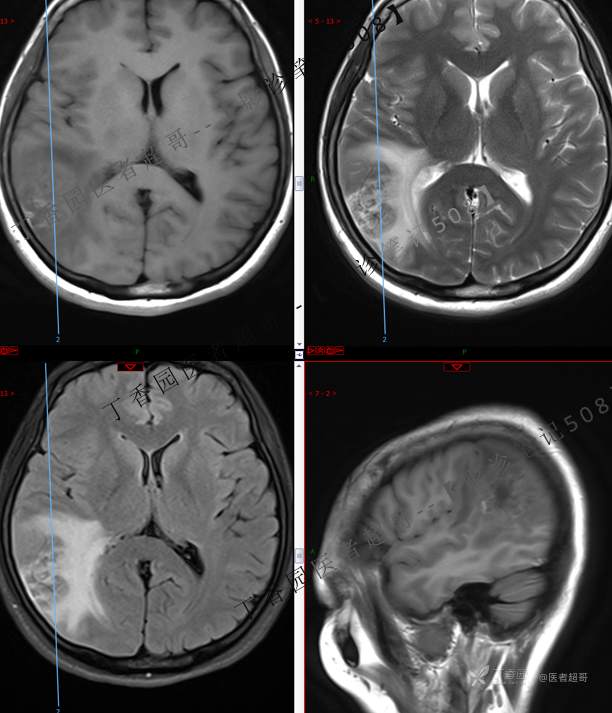

【影诊笔记508】同病异影,个人感觉有难度,欢迎分析,领丁当!有详细术程及病理!

患者性别:女

患者年龄:46岁

主 诉:突发一过性意识不清伴肢体抽搐5天余。

现病史:患者5天余前无明显原因及诱因出现一过性意识不清,伴肢体抽搐,持续约2-3分钟,后意识逐渐恢复,无明显头痛头晕,无恶心呕吐,无肢体抽搐,无呼吸困难,无二便失禁,后就诊于当地医院,行颅脑CT示“颅内占位性病变”,予以药物对症治疗,具体不详,门诊以“颅内占位性病变”,收入我科。患者自发病以来,未进饮食,近期体重无明显变化。